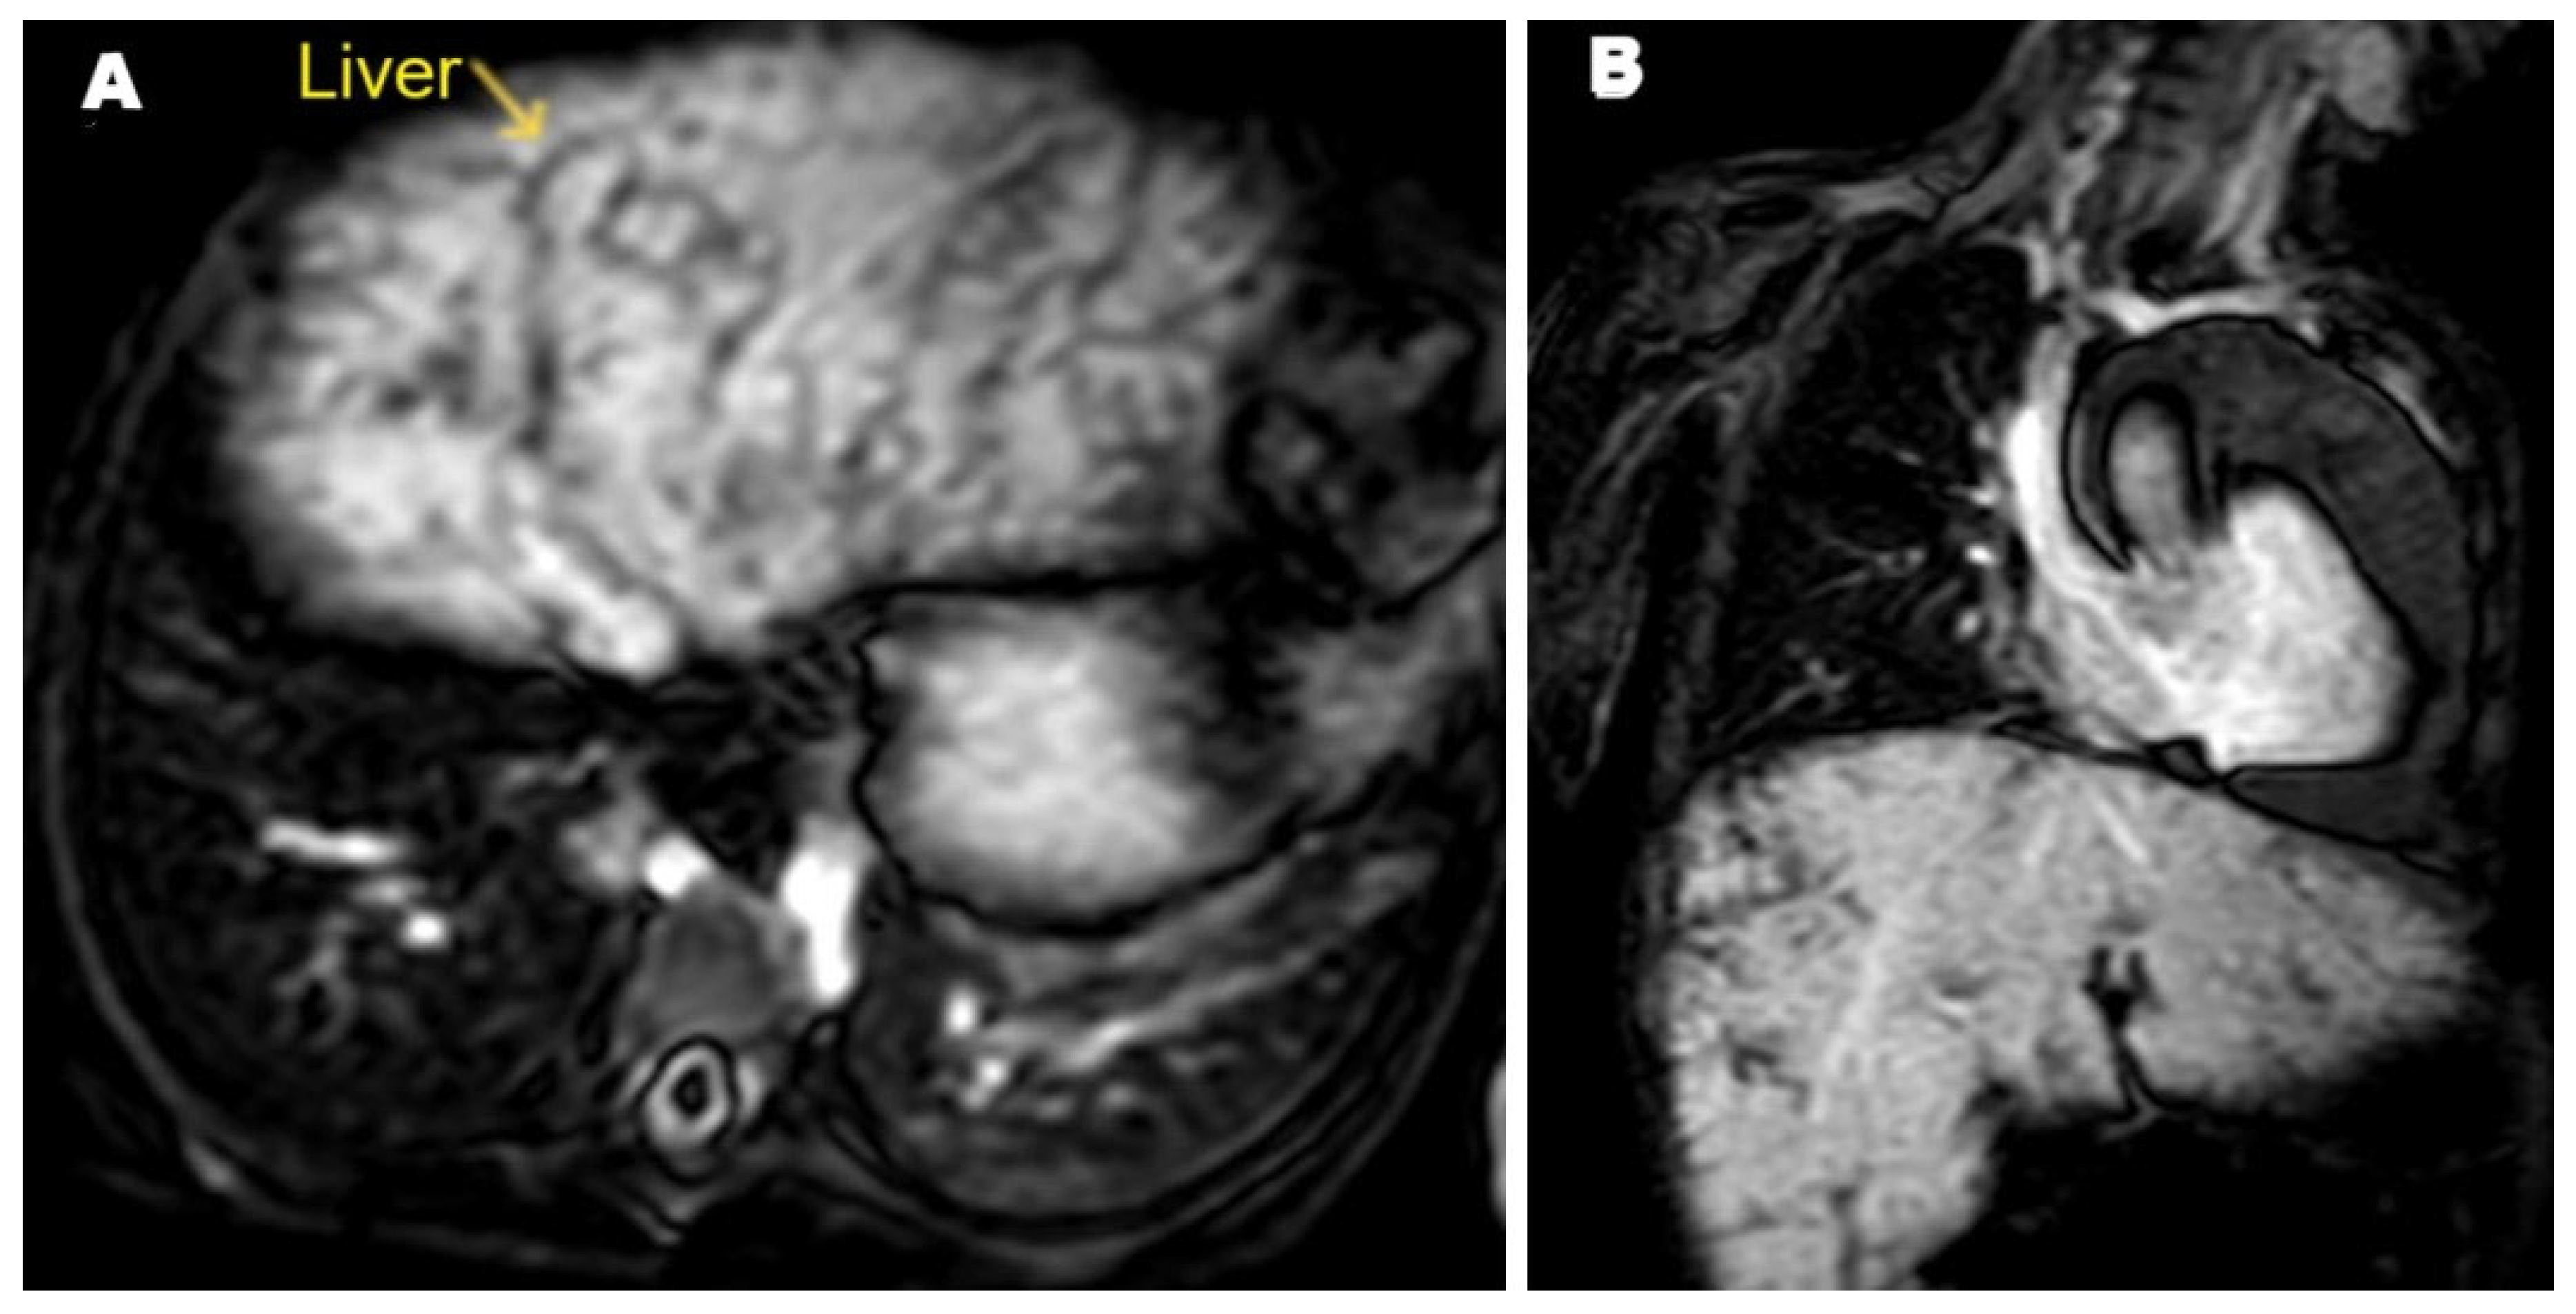

2. Case Presentation